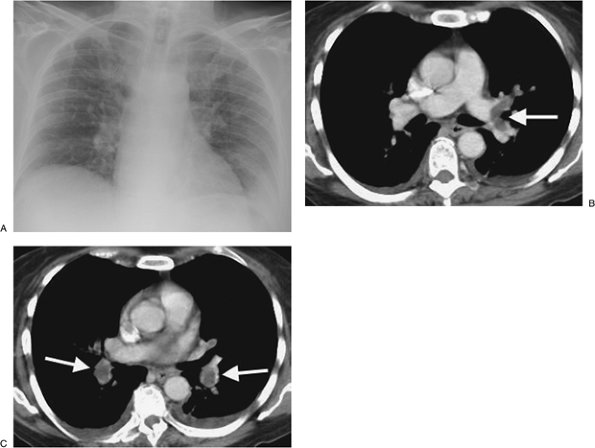

FIGURE 17-5. Acute PE. A: CTPA of a 78-year-old woman shows an intraluminal filling defect surrounded by contrast material in the proximal right lower lobe pulmonary artery (arrow). B: Coronal CTPA shows that the intraluminal filling defect extends from the proximal right lower lobe pulmonary artery inferiorly to distal branches (arrows). C: CTPA with lung windowing shows oligemia and diminution of vessels on the right (Westermark sign).

FIGURE 17-6. Acute PE. A: Posteroanterior (PA) chest radiograph of a 52-year-old woman with cholangiocarcinoma shows a rounded opacity at the left costophrenic angle, representing a Hampton hump of pulmonary infarction. B: CTPA shows a saddle embolus bridging the lingular and left lower lobe pulmonary arteries (arrow). C: CTPA at a more inferior level shows intraluminal filling defects expanding the proximal lower lobe pulmonary arteries (arrows).